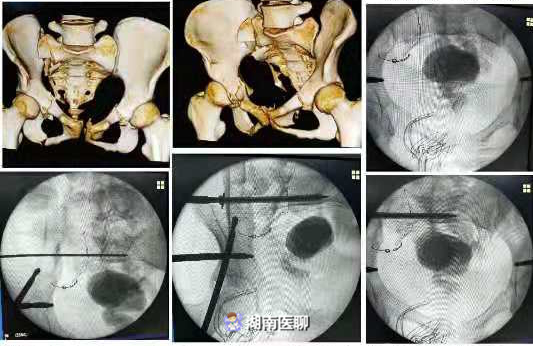

1、骨盆骨折,Tile 分型 C1 ,右髂骨骨折,双侧耻骨上下支、体部骨折,骶骨右侧骨折,右侧骶髂关节半脱位。

骨二科主任罗志顺介绍,患者的情况属于侧翻挤压型骨盆重度损伤,骨盆前后方都有骨折,说白了,就是整个骨盆都被撞散了。

罗志顺主任在广东省中医院周琦石教授和葛洪庆教授的指导下,开展了郴州中医系统首例“闭合复位+经皮S1空心钉内固定术+骨盆前环外固定支架固定术”。

整个手术历时3个小时,出血仅几十毫升,成功复原了患者的骨盆。